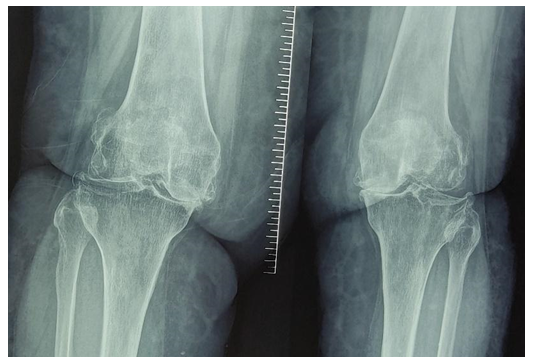

In the course of the research, the results of TKE in 147 patients and the outcomes of their medical, social, and vocational rehabilitation were analyzed. In addition, we studied the leg SDF to evaluate the dynamics of the operated knee disability, postoperative functions, and patient work capacity since the degree of the SDF recovery associates with frequency, complexity and duration of rehabilitation.In the diagnosis of knee joint pathology, an X-ray examination is the main objective method that gives physicians the information to determine the tactics and results of surgical treatment. | Figure 2. Patient S., female, born in 1965. Radiography of the knee in direct and lateral projection before surgery (osteoporosis, knee deformity) |